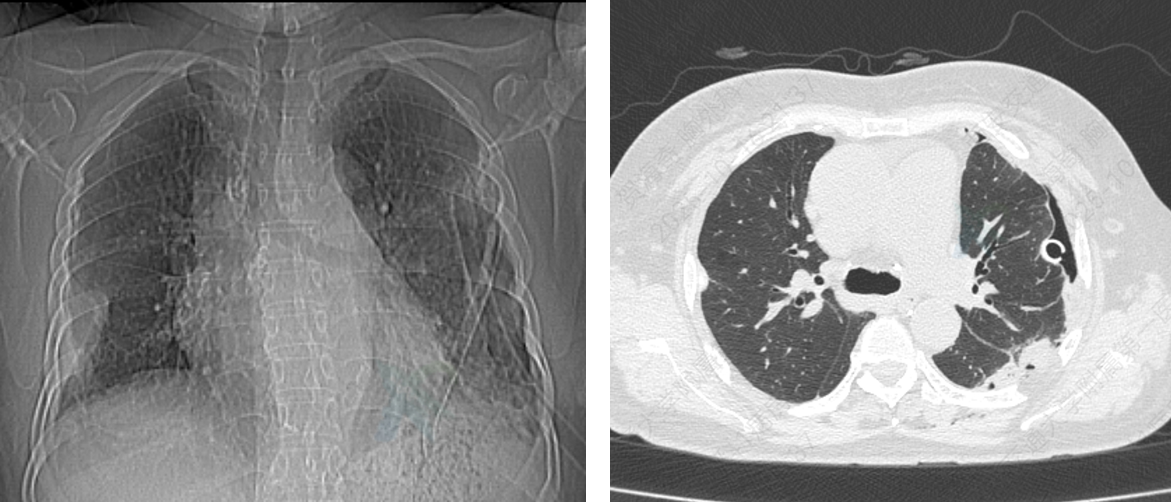

术后第一天,李女士即表示胸口压迫感消失,呼吸明显顺畅。在胸外科团队精心护理与加速康复理念指导下,她术后第二天即可下床活动,身体日渐好转,术后第八天康复出院。

图3 术后CT检查显示左肺已完全复张